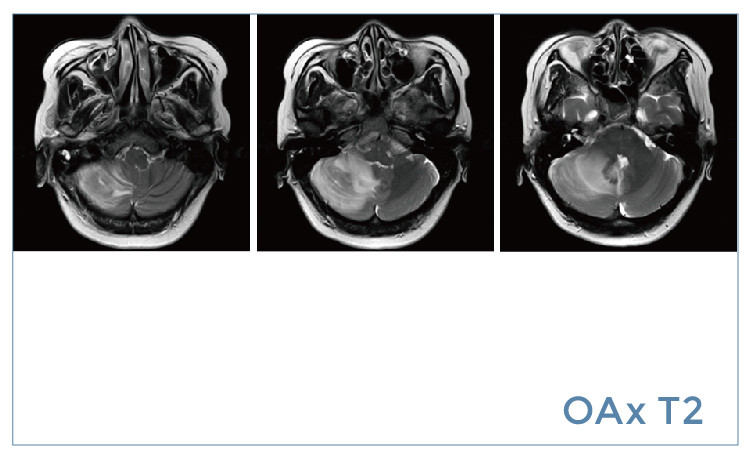

【朗润影像档案】20190802磁共振影像病例结果讨论

【朗润影像档案】磁共振影像病例分享(编号20190802)